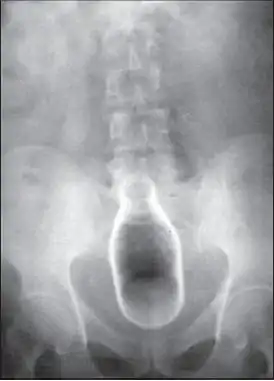

Обычно делают несколько рентгеновских снимков, чтобы точно определить место нахождения инородного тела. Инородные тела из малоконтрастного материала (например, пластика) могут потребовать ультразвукового исследования или компьютерной томографии.[28] Магнитно-резонансная томография противопоказана, особенно если неизвестен материал инородного тела. Инородные тела прямой кишки могут проникать глубоко в толстую кишку, при определенных обстоятельствах вплоть до правого изгиба ободочной кишки.[9]